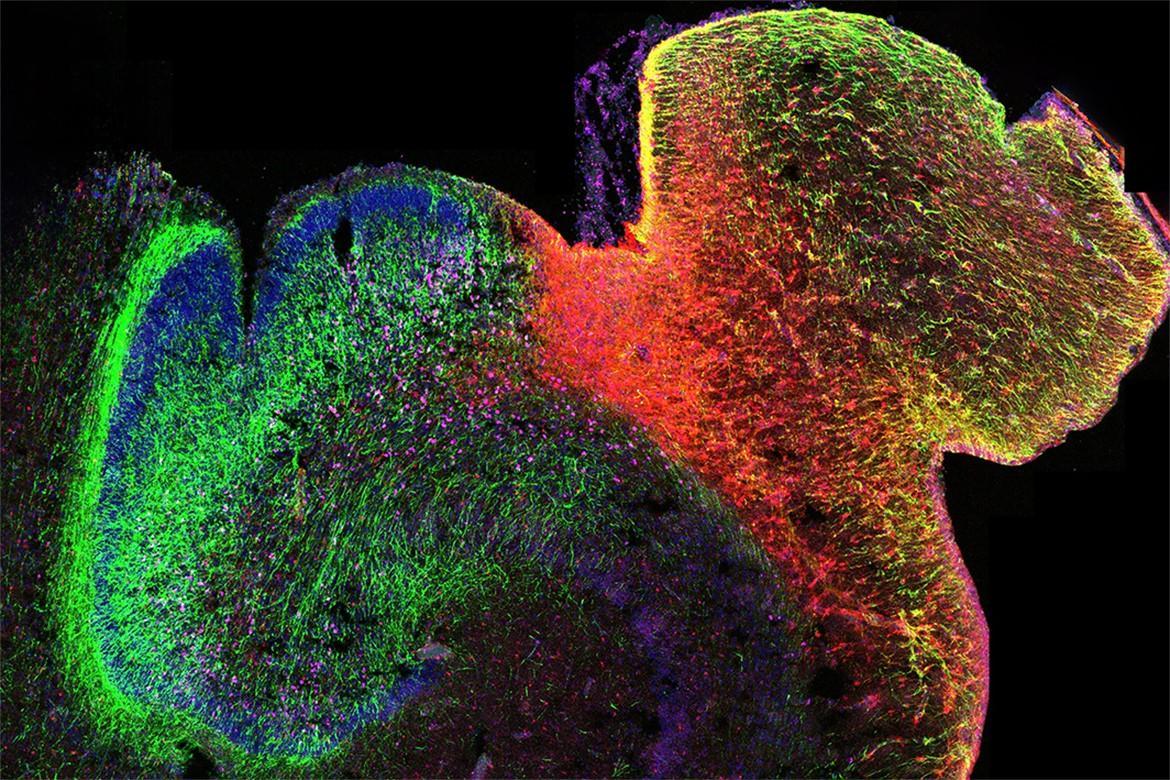

由美国加州大学洛杉矶分校牵头的一项研究,揭示了人类大脑发育过程中基因调控的演变方式,并展示了染色质的3D结构在其中发挥的关键作用。研究人员绘制了海马体和前额叶皮质中DNA修饰的首张图谱,这两个大脑区域对学习、记忆和情绪调节至关重要,也常与自闭症和精神分裂症等疾病相关。这项研究为早期大脑发育如何影响身心健康提供了新的见解。相关研究9日发表在《自然》杂志上。

为了绘制该图谱,研究人员采用了一种尖端测序方法,即单核甲基化测序和染色质构象捕获技术,能同时分析控制单个细胞基因表达的两个表观遗传机制。搞清这两个调控机制如何作用于影响发育的基因,是理解这一过程出错而导致神经和精神疾病的关键步骤。

研究人员分析了从中期妊娠到成年期的供体提供的超过53000个脑细胞,揭示了关键发育窗口期间基因调控的重大变化,构建出人类大脑发育关键时间点发生的巨大遗传重组的全面图景。